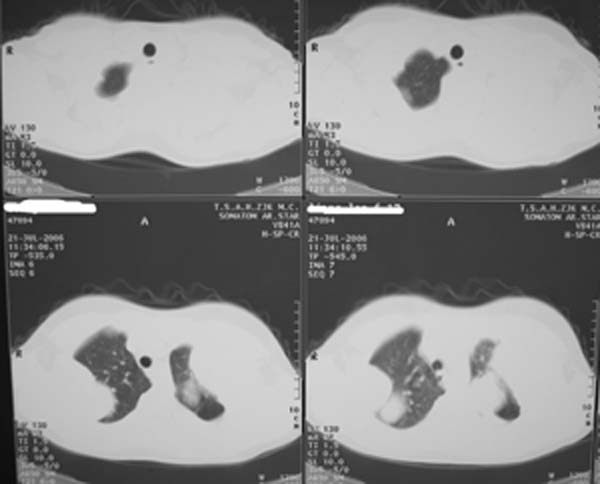

女性,17岁,一年前因股骨病变截肢,现胸憋。

股骨下段针状瘤骨垂直于骨皮质向外生长.并见软组织密度肿块影.骨髓腔密度增高.考虑股骨下段成骨肉瘤.胸膜及左肺转移瘤.

左肺巨大肿块,内散在斑点状高密度骨化影,右肺见多发结节灶,双侧胸膜局限性增厚。有骨肉瘤病史,支持骨肉瘤手术后转移。